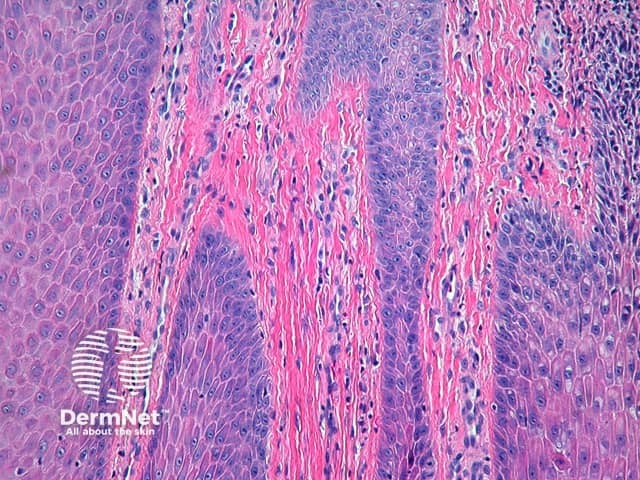

In chronic spongiotic dermatitis, the degree of spongiosis is often mild and difficult to appreciate. Vesiculation is uncommon. There is significant epidermal acanthosis, which may show a psoriasiform pattern with hyperkeratosis, hypergranulosis and minimal parakeratosis. Fibrosis of the papillary dermis may be present (figure 3).

Figure 3